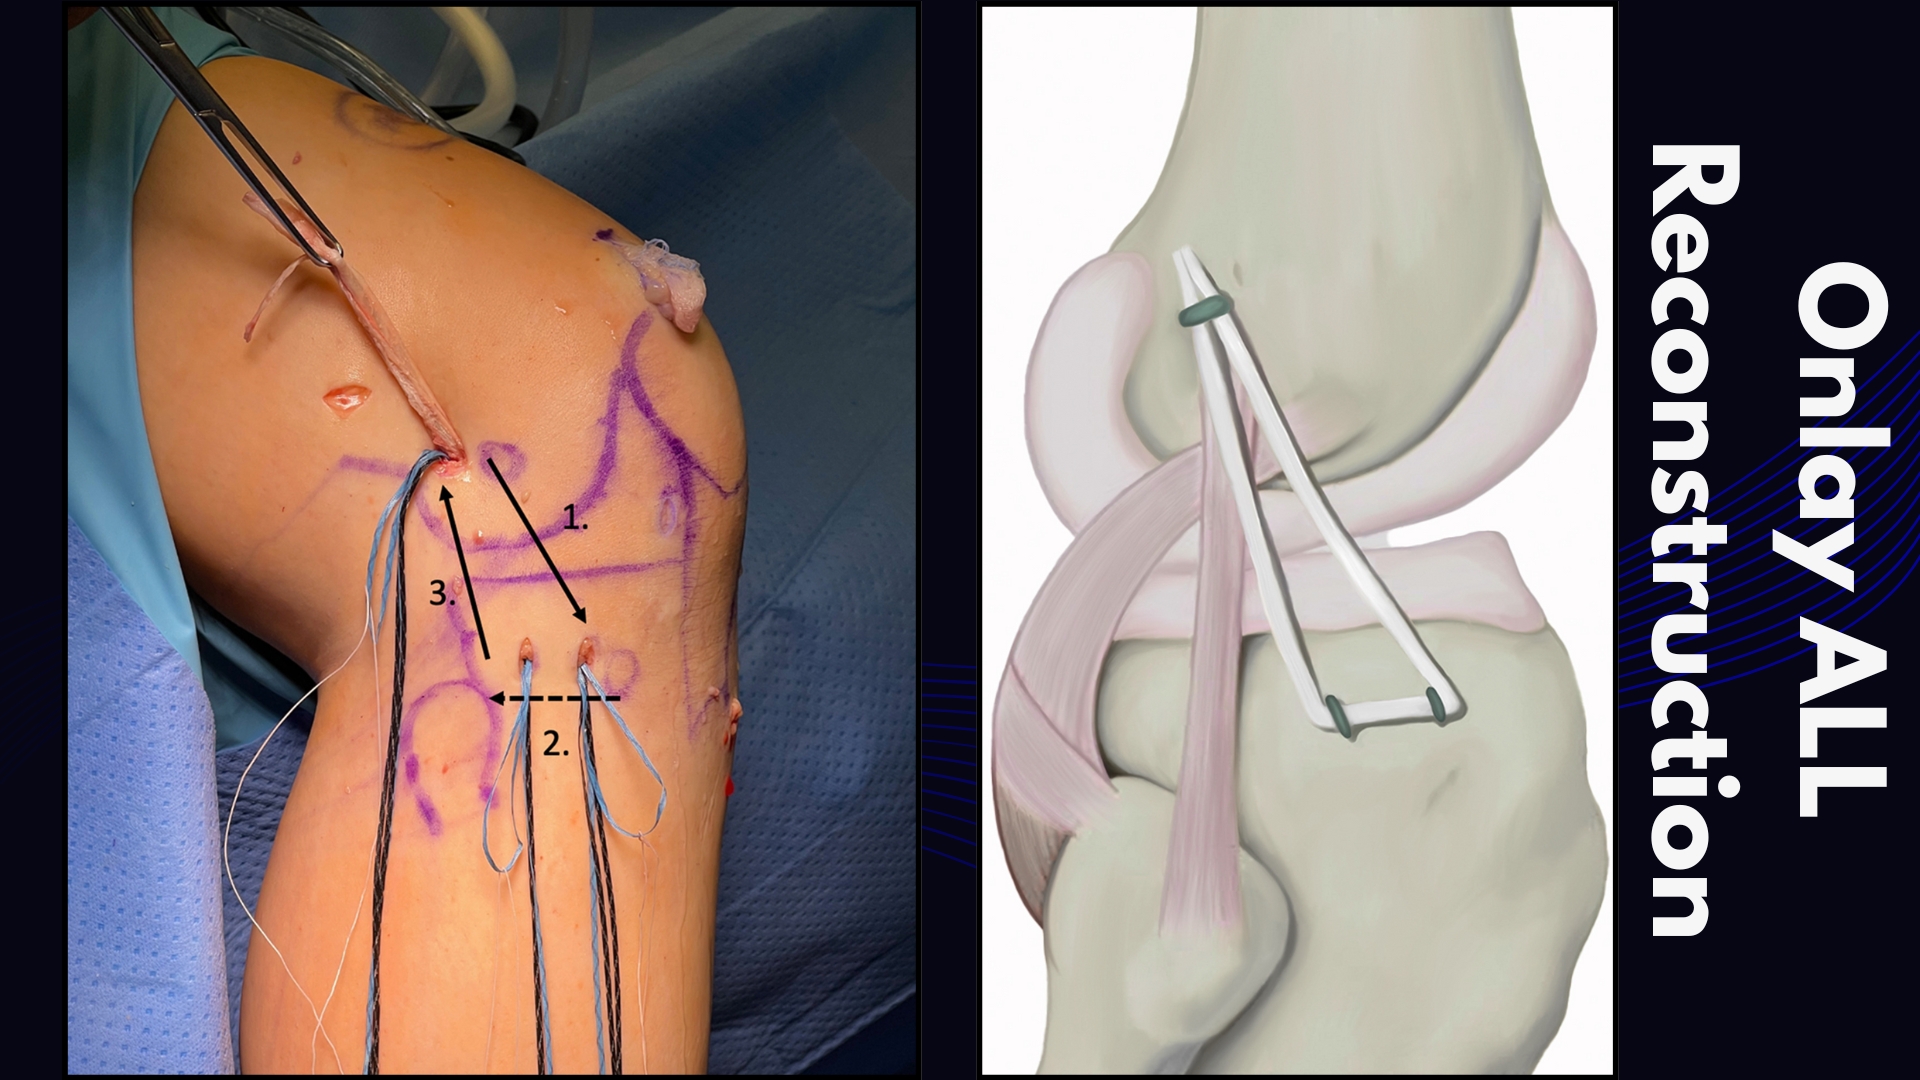

- Onlay ALL Reconstruction

| Fixation | Fixation to bone surface (tenodesis) | Full bone tunnel | Shallow socket (onlay) |

| Anatomical Accuracy | Non-anatomic (functional restraint) | Anatomical | Anatomical (simplified) |

| Fixation Method | Distal attachment to bone, proximal end fixed with staple/screw/anchor. | Proximal and distal ends fixed within bone tunnels. | Proximal end fixed to the surface of the bone with anchors/screws; distal end may be in a tunnel. |

| Primary Advantage | Proven, effective, and technically simpler. Avoids the need for a separate free graft. | Aims for a more precise anatomical reconstruction. | Avoids tunnel convergence with the ACL graft, a major technical benefit. |

| Tunnel Convergence Risk | Minimal | Higher | Minimal |

| Key Limitation | Risk of over-constraint | Risk of tunnel convergence | Graft specificity, technical complexity |

| Ideal Use Case | Primary & revision cases, high-grade pivot shift | Surgeons prioritizing anatomy, primary cases | Revision surgery, multi-ligament injuries, narrow femurs |

- Onlay ALL Reconstruction simplifies the procedure, offering practical advantages by avoiding tibial tunnel drilling while maintaining comparable stability.